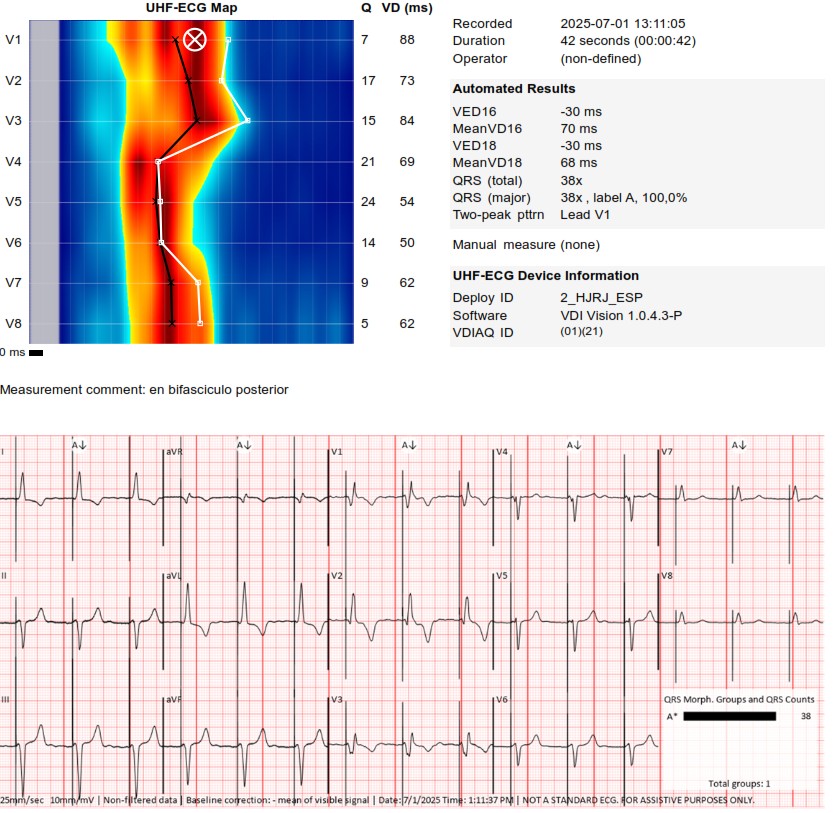

I strongly support HBP, but in this case,the great improvement in QRS didn't correct the asynchrony measured with UHF ECG.We opted for LBBAP despite the RV delay.The final programming AV 70 ms and fusion with native rhythm achieved the best result with UHF ECG(very useful tool)

These are UHF maps of the two patterns. The second one is a little bit deeper into the septum,